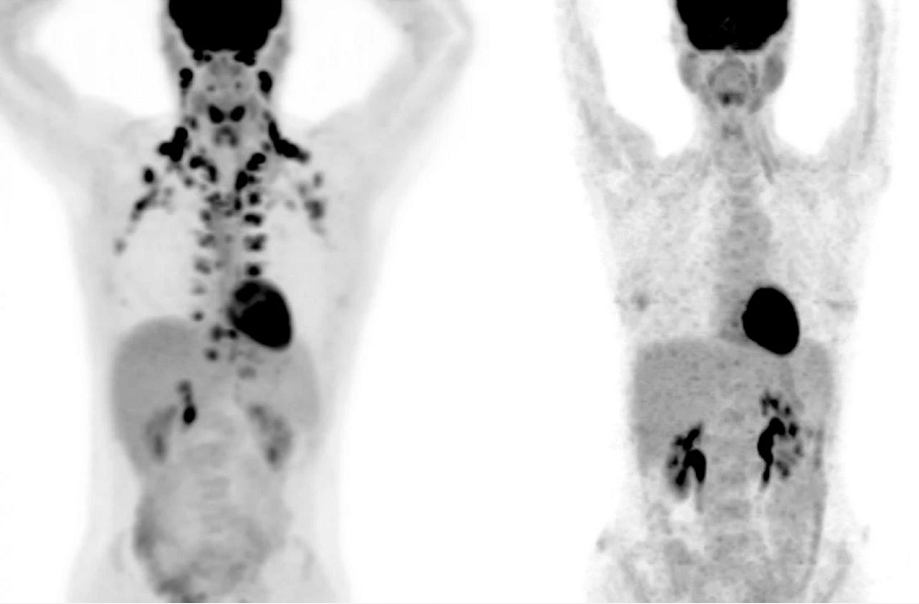

左图是颈部和锁骨部位有棕色脂肪的人,右图则没有(图片来源:MSKCC  Andreas G. Wibmer & Heiko Sch?der)

Beche意识到,这里或许是一个真正有大量BAT样本数据的资源库。在与对方沟通合作过后,Beche拿到了病人的PET扫描数据,一共有超过5.2万名病人的13万张扫描图。根据记录,有BAT的PET扫描图占总数的5.9%,这些图来自5000多名病人,也就是大约10%的病人显示存在BAT。